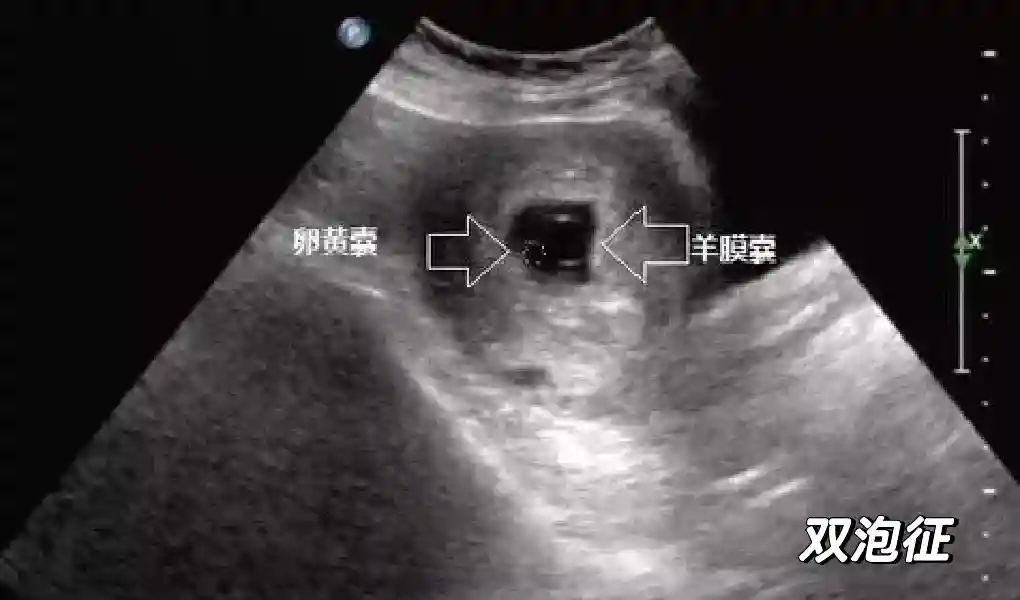

5️⃣羊膜:早孕期羊膜囊菲薄,超声常不能显示。孕7周以后加大增益或者用高频超声可以显示羊膜。羊膜囊位于绒毛膜内,胚胎位于羊膜囊内。随着胚胎增长,羊水增多,羊膜囊增大,孕12-16周时,羊膜与绒毛膜全部融合,胚外体腔消失。宫腔线一侧内膜内一圆形增强回声区,中央有小囊状液性暗区,宫腔线局部突起变形,称蜕膜内征,用于判断早早孕。#超声 #早孕检查 #妊娠